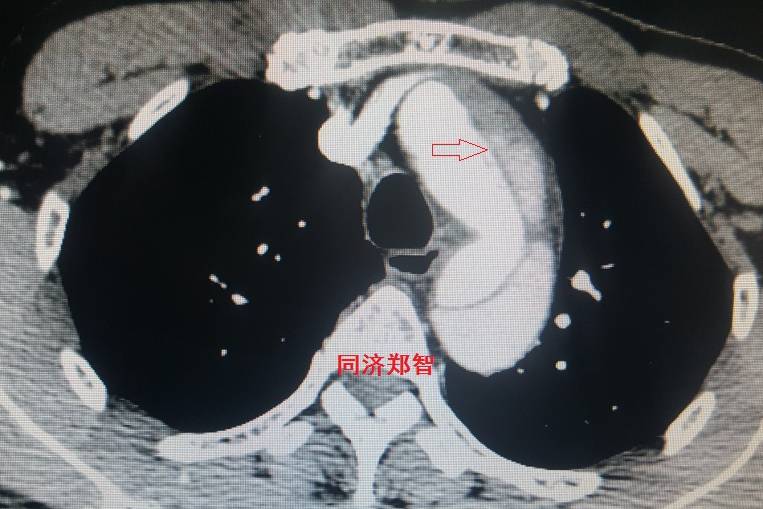

平扫CT提示主动脉弓层面及右肺动脉层面均可见主动脉血管腔内的内膜片影(红色箭头所示),CTA显示为A型主动脉夹层。

病例六